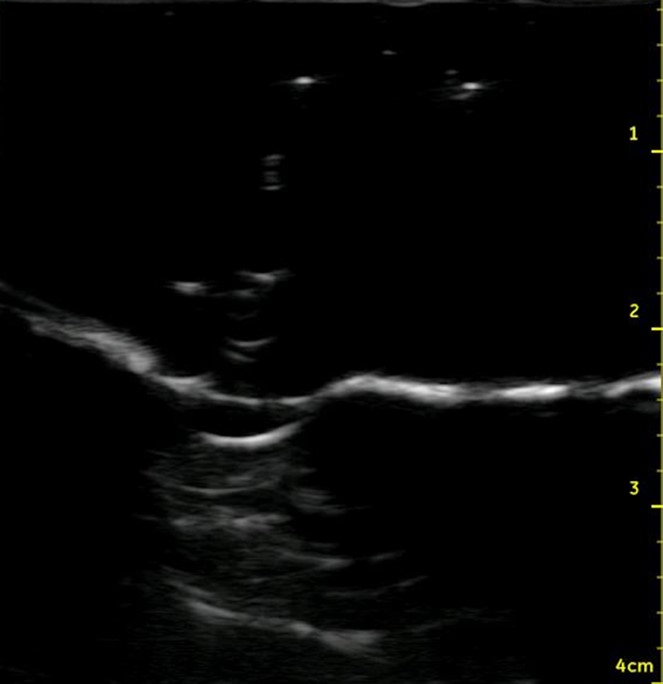

Figure 6. Midsagittal ultrasound of the anterior neck of a live person

Figure 7. Midsagittal ultrasound of the anterior neck of the model

In contrast to native cartilage, which is hypoechoic with posterior shadowing, the plastic model of the thyroid cartilage and cricoid cartilage appear hyperechoic with more dense posterior shadowing (below). This model performs well as an ultrasound-guided cric training model. It has realistic anatomy. It models a patient with difficult to palpate anatomy, which are patient who may be difficult to intubate and may be more likely to need cricothyrotomy in the first place. The overlying skin and pre-tracheal ballistic gel can be easily and quickly replaced for the next operator in a training setting. The model allows for performing all the steps of cricothyrotomy including passing the bougie and ETT. The model is durable and re-usable.